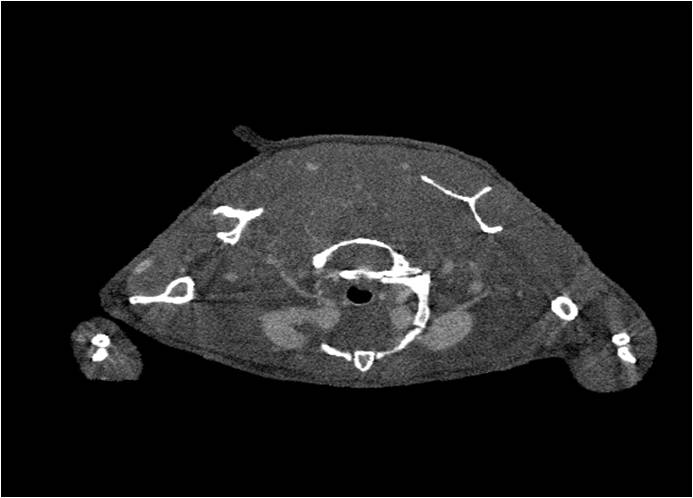

胸部和心血管的層析成像 胸部和心血管的3D圖像

心血管.jpg 心血管1.jpg